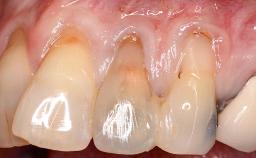

Periodontal Plastic Surgery and Prosthetic Procedures to Treat Peri-Implant Soft-Tissue Dehiscences

A 30-year-old woman was referred by her general dentist for evaluation of an esthetic complication related to previous implant treatment for congenitally missing maxillary lateral incisors. The patient’s chief complaint was the inadequate esthetic appearance of her smile. The case demonstrates the use of a combined approach to achieve optimal results. Two different flap designs - a tunnel technique and a coronally advanced flap - are employed based on the surgical objectives for the affected site.